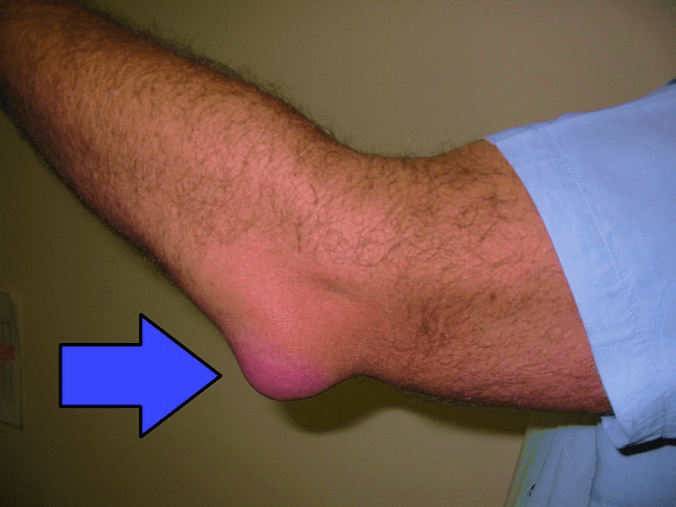

- Swelling: The most noticeable symptom is a visible swelling at the back of the elbow, which can vary in size from small to as large as a golf ball.

- Pain: While some cases may be painless, others experience pain, especially when bending the elbow or applying pressure to it.

- Warmth: The affected area may feel warm to the touch.

- Redness: The skin over the swollen area might appear red, particularly in cases of infection.